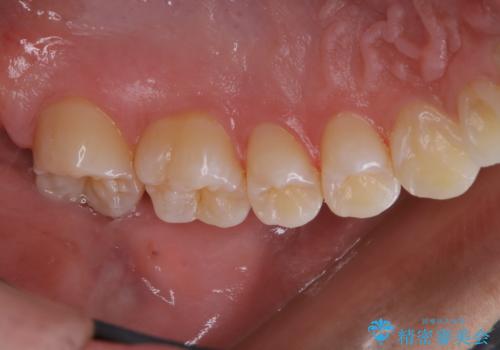

3カ月に1度のPMTCでオーラルケア

- 3カ月ごとに定期的にメンテナンスにいらしている方です。PMTC30分コースを行いました。

PMTC(保険外治療)は、毎日の歯磨きで落としきれない汚れや、タバコのヤニなどの着色も除去します。目には見えない歯と歯の間・歯肉の境目などに残っているプラーク(歯垢)もしっかり取り除きます。